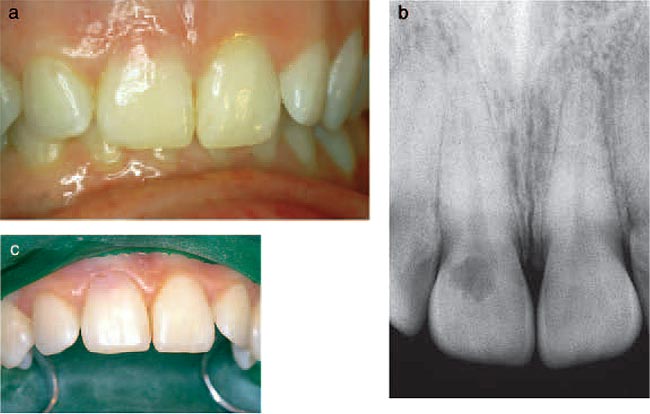

Fig. 4. (a) Labial view of the anterior teeth of a 28-yearold female who

had received fixed orthodontic treatment 14 years earlier. The maxillary

right incisor shows a pink discoloration near the gingivalmargin. (b) The

radiograph of the maxillary right incisor reveals an irregular radiolucency

overlying the root canal outline. From (20). Reproduced with permission

from Quintessence Publishing. |

Class 2

Invasive resorptive lesions of this class may present with a pink discoloration

of the tooth crown (Fig. 4a), while the radiographic image usually shows a surprisingly

extensive irregular radiolucency extending from the cervical area into the tooth

crown and projected over the root canal outline (Fig. 4b). If the lesion is proximally

located the radiographic image will show ar adiopaque line bordering the pulp

space. An examplec an be seen in a radiograph of the maxillary central

incisors of a 22-year-old male who had a history of extensive orthodontic treatment

in his teens (Fig. 5a).W hile this image is similar to that of dental caries,

it

differs in that the outline is slightly more irregular. The clinical appearance

of the palatal surface of this patient postulated that pulpitic symptoms only

develop when the resorption ultimately penetrates through this barriera nd is

secondarily invaded by oral microorganisms.E vidence for the presence of an anti-invasion

factor in predentin has been presented (21) and provides ane xplanation for this

uniquely interesting protectiveb arrier observed in this active formof tooth

resorption.

Fig. 5. (a) Radiograph of the maxillary central incisors of a 22-year-old

male. Extensive radiolucent areas extend close to the pulp spaces. Although

similar in appearance to carious lesions, the margins are somewhat irregular.

The pulp space is bordered by a radiopaque line which is more evident in

the right incisor. The invasive cervical resorptive lesion is classified

Class 2. (b) Palatal surfaces of the maxillary central incisors. Pinkish

area are visible near the mesial cervical regions, particularly evident

in the right incisor. From (1). Reproduced with permission from Quintessence

Publishing.